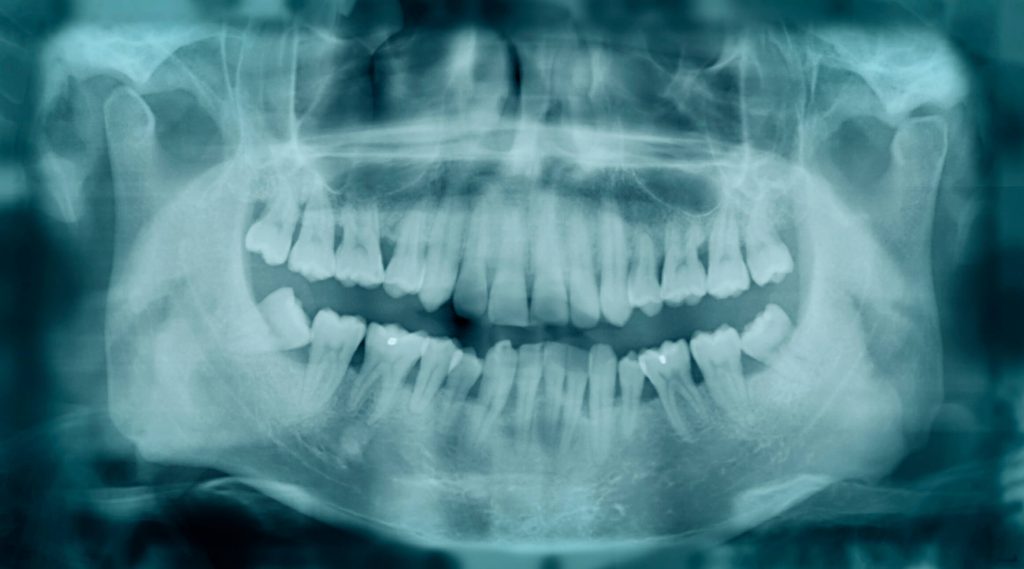

Estética dental: 5 tratamentos incríveis que você deve conhecer

Um belo sorriso abre portas para uma série de oportunidades, garantindo ainda a manutenção da autoestima. Por isso, cada vez mais pessoas têm recorrido à estética dental para melhorar a qualidade de vida e recuperar